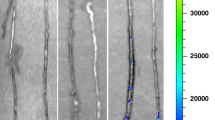

a Representative confocal images of enteroids harvested from wild-type (WT) and AHR knockout (Ahr-/-) mice after 7 days of culture on Matrigel, and stained with the epithelial marker (Ecadherin, Ecad, green signal), actin filaments (Rhodamine Phalloidin, RP, red signal), and nuclei (DAPI, blue signal). b, c qRT-PCR showing the expression of Cyp1a1 (b, n = 3, 3, 3, 3 wells of enteroids, WT -I3C vs WT + I3C p = 0.0208) and Tnf-α (c, n = 3, 3, 3, 3 wells of enteroids, Ctrl vs WT LPS p < 0.0001, WT LPS vs WT LPS + I3C p = 0.0258) in these enteroids under the indicated condition (200 μM I3C pretreatment overnight and then LPS treatment (50 μg per mL) for 4 h). d, e Representative confocal images (d) and quantification of fluorescent intensity of NF-κB translocation (e, n = 81, 48, 48, 50 enteroid cells, Ctrl -I3C vs LPS -I3C p < 0.0001, LPS -I3C vs LPS + I3C p < 0.0001). NF-κB, green signal; actin filaments (Rhodamine Phalloidin, RP, red signal); nuclei (DAPI, blue signal). f–i qRT-PCR showing the expression of Cyp1a1 (f, n = 6, 8, 9, 8 mice, WT -I3C vs WT + I3C p = 0.0042), Il6 (g, n = 6, 7, 8, 8, 8 mice, Ctrl vs WT LPS p = 0.0018, WT LPS vs WT LPS + I3C p = 0.0065), Tnf-α (h, n = 6, 7, 8, 8, 8 mice, Ctrl vs WT LPS p = 0.0036, WT LPS vs WT LPS + I3C p = 0.0017) and Tlr4 (i, n = 18, 19, 9, 8 mice, WT -I3C vs Ahr-/- -I3C p = 0.0013, WT -I3C vs WT + I3C p = 0.0033) in the ileum of newborn mice after treatment with or without I3C (25 mg per kg body weight per day for 4 days). j, k qRT-PCR showing the expression of the Tlr4 regulatory microRNAs, miR-146b (j, n = 7, 5, 8, 5 mice WT -I3C vs WT + I3C p = 0.0300), let-7i (k, n = 6, 5, 7, 5 mice WT -I3C vs WT + I3C p = 0.0016) and miR-223 (l, n = 7, 5, 8, 5 mice WT -I3C vs WT + I3C p < 0.0001) in the ileum of WT and Ahr-/- mice in the presence or absence of I3C (25 mg per kg body weight for 24 h). m, n qRT-PCR showing expression of CYP1A1 (m, n = 3, 3, 3, 3 wells of human explant culture, Ctrl -I3C vs Ctrl +I3C p = 0.0147, LPS -I3C vs LPS + I3C p = 0.0096) and TNF-α (n, n = 3, 3, 3, 3 wells of human explant culture, Ctrl -I3C vs LPS -I3C p = 0.0003, LPS -I3C vs LPS + I3C p = 0.0218) in the presence of I3C (200 μM I3C pretreatment for 15 min and then additional 6 h) and LPS (50 μg per mL for 6 h). Scale bars in a, 25 μm. Scale bars in d, 10 μm. All data are presented as mean values ± SEM. *p < 0.05, **p < 0.01, ***p < 0.001, p values obtained either from two-sided t tests or one-way ANOVA followed by multiple comparisons. Each dot in graphs represents data from an individual well of enteroids culture, an individual enteorid cell of NF-κB staining, an individual mouse, or an individual well of human explant culture.

To investigate directly whether AHR activation could limit TLR4 signaling in the intestinal epithelium, we next performed studies in primary enteroids derived from both wild-type and Ahr-/- mice (Fig. 4a). Treatment of enteroids with I3C induced the expression of Cyp1a1 in wild-type but not Ahr-/- enteroids (Fig. 4b), confirming that AHR is appropriately activated on intestinal epithelial cells. Importantly, I3C significantly reduced the LPS-mediated induction of Tnf-α in wild-type but not Ahr-/- enteroids (Fig. 4c), consistent with a reduction in TLR4 signaling in intestinal epithelial cells in vitro. As shown in Fig. 4d, e, I3C treatment significantly reduced LPS-induced translocation of the downstream transcription factor NF-κB from the cytoplasm to the nucleus in these enteroids, providing an additional measure of TLR4 inhibition.